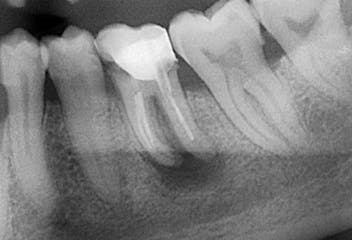

Le cisti possono originare da infezioni latenti di denti malati oppure residui embrionali e radici che sono rimaste inclusi (imprigionate) nelle strutture ossee. L'intervento chirurgico che consiste nell'eliminazione dell'agente colpevole del processo infiammatorio garantisce una guarigione permanente. La terapia è indolore poichè eseguita sotto anestesia locale. Raramente una biopsia (prelievo) del tessuto si rende necessaria per uno studio istopatologico, atto a corroborare la diagnosi sospetta e pianificare se necessario ulteriori trattamenti complementari